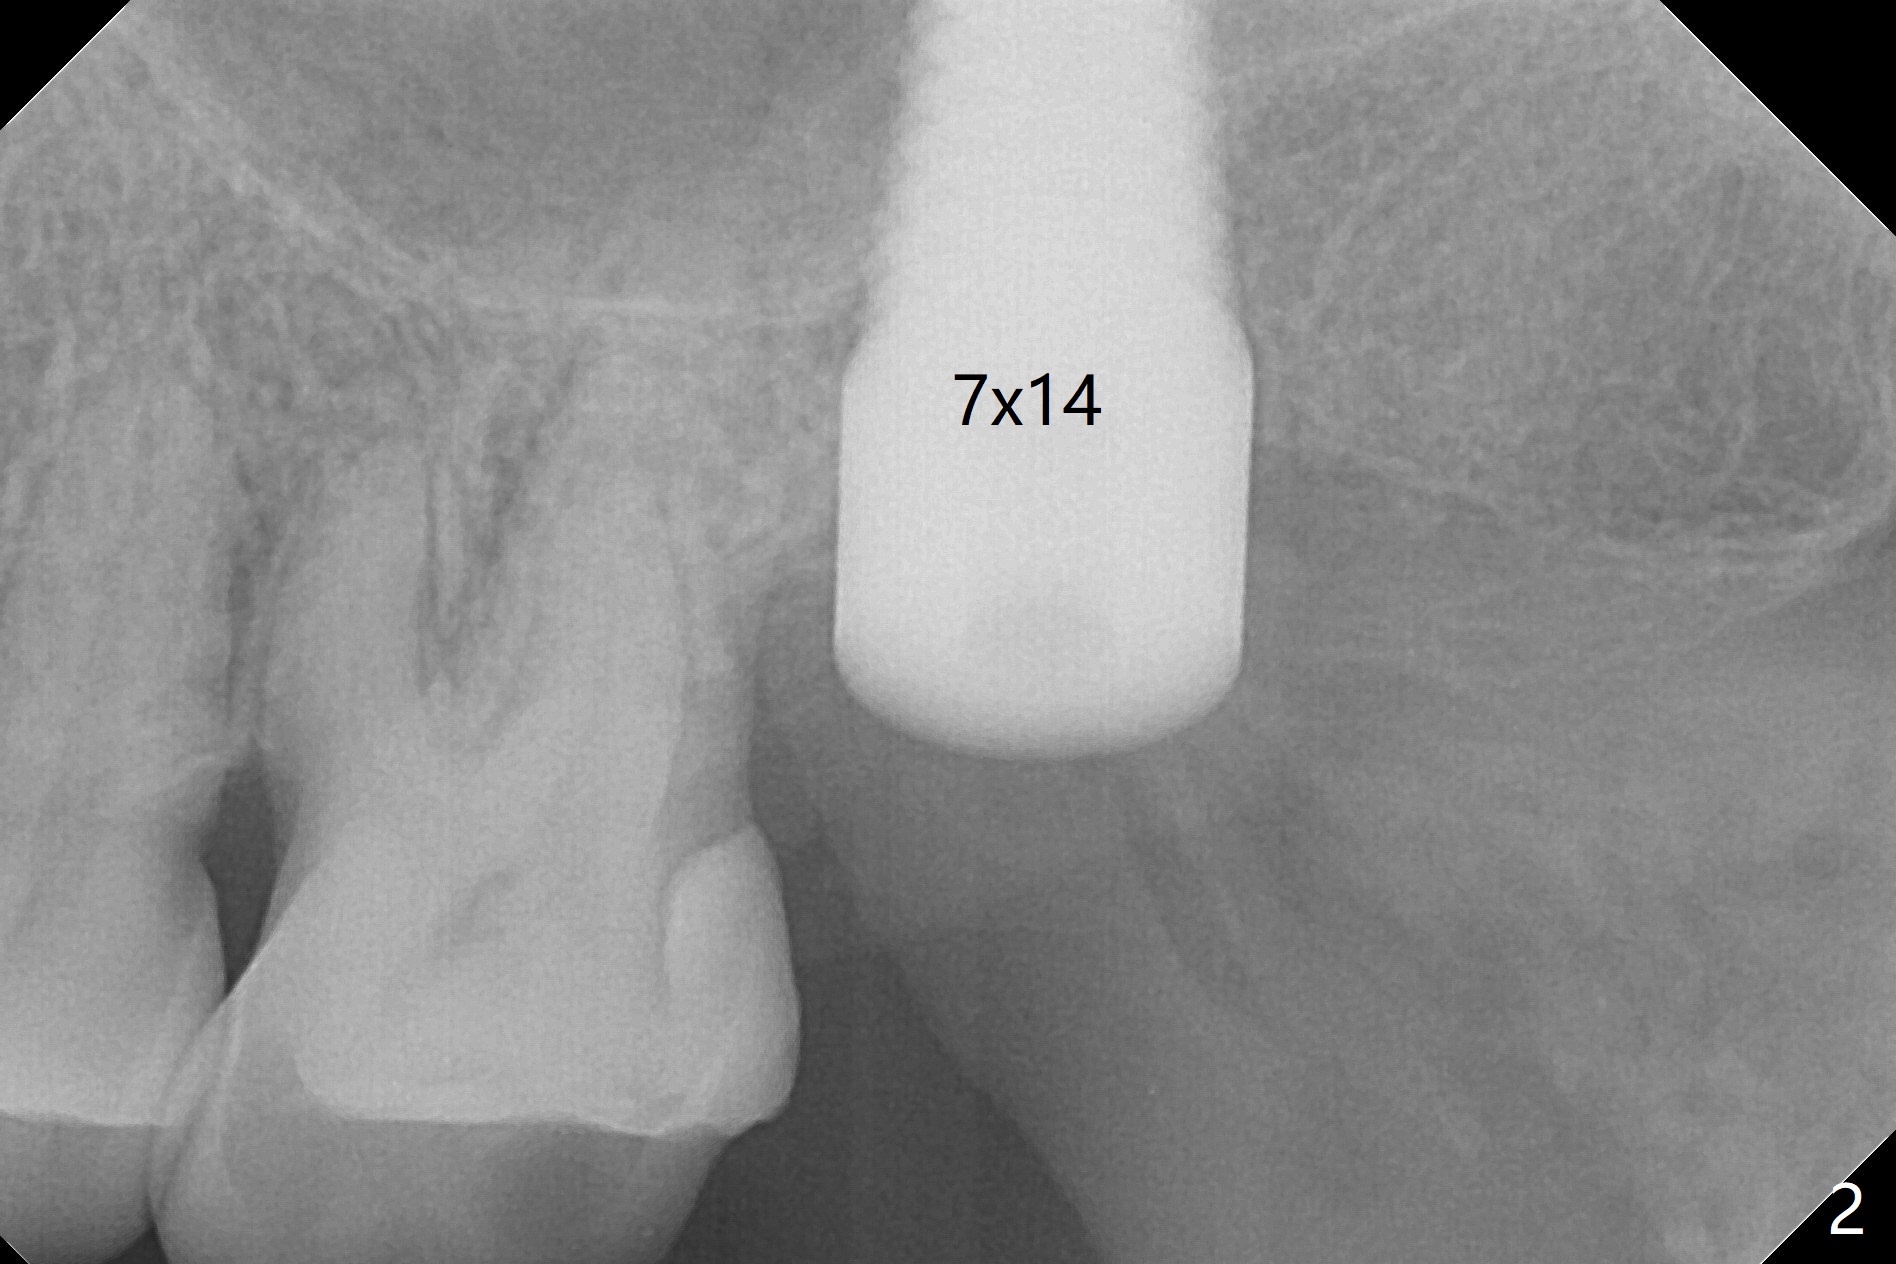

A 56-year-old woman has sign of periimplantitis 2 years 9 months post cementation. After incision, the 5.5x13 mm bone-level implant is ~ 3 mm inferior to the buccal crest. The implant is removed with 7/6 mm trephine bur, elevator and implant driver. The sinus membrane perforates. A 8x17 mm tap achieves stability (Fig.1), but the peripheral bone seems to be thin. Although a 7x14 mm tissue-level implant has stability, it is placed too deep (Fig.2). Following insertion of a piece of Osteogen plug for sinus membrane repair, a 8x14 mm implant is placed with >40 Ncm with allograft placed around the unpolished portion of the implant (Fig.3,4). A 6x3 mm abutment is placed to hold periodontal dressing in place. Because of the abutment with a slot (Fig.5 A), the periodontal dressing remains in place 4 days postop before the patient travels back home for 4 hours. In fact there is no postop sinus infection; the implant threads seems not be exposed 3 months postop (Fig.6). Because of the large implant, it is loaded early (Fig.7, 8 (Temp Bond)). Upper Molar Immediate Implant, Trajectory II 劈开术 Xin Wei, DDS, PhD, MS 1st edition 08/09/2019, last revision 04/11/2021